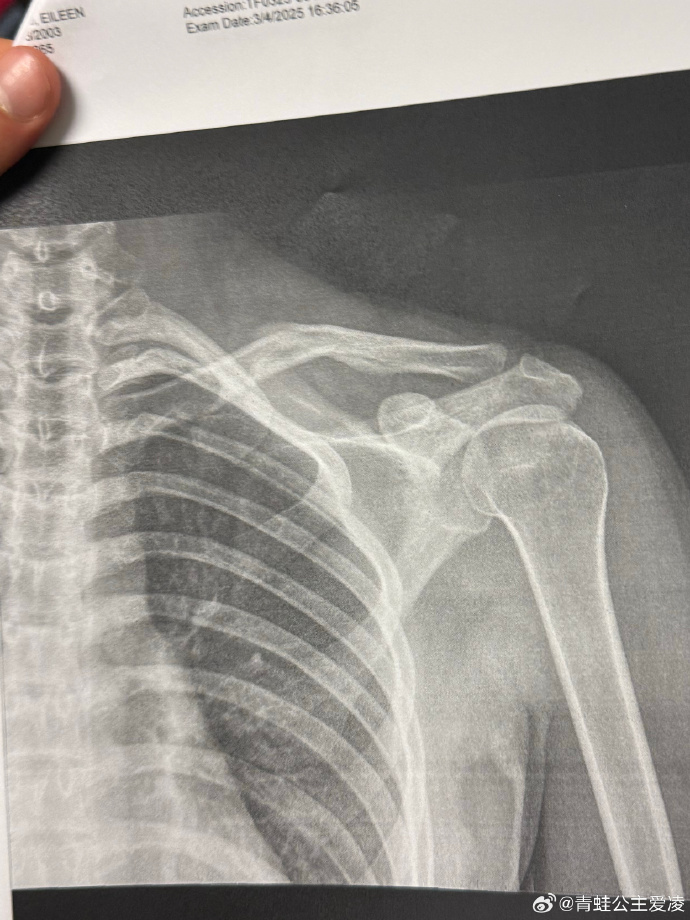

2025年3月9日,谷爱凌在社交媒体晒出肩部骨折的X光照片,并配上一个心碎的表情,随后相关话题登上热搜。